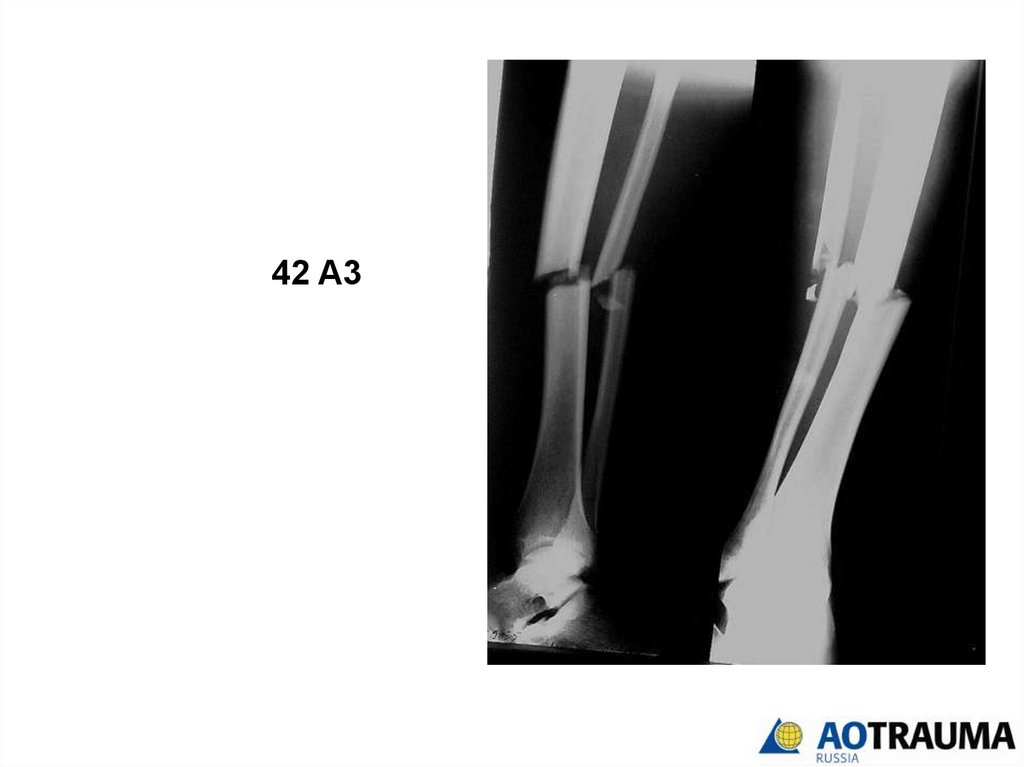

Кость - 4

Сегмент

Тип

группа

32.

Сегмент - 2

33.

Тип - А

34.

Группа - 3

35.

42 A3